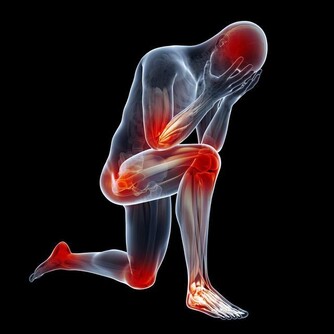

目前中國有1億人左右患有靜脈曲張,靜脈曲張的問題不僅僅是看上去不雅觀,更重要的是,當靜脈曲張累積到深靜脈時,或引起肺栓塞,導致猝死。

所以我們應該對靜脈曲張保持足夠的警惕,及時干預,防止出現深靜脈血栓,增加猝死的風險。因此,今天,我們主要講講靜脈曲張的預防。

讓我們先來回想一下,靜脈曲張的形成原因主要有哪兩個?一是先天性的血管壁薄弱,這一點我們沒法干預;另外一個原因是久坐久站,姿勢不正確。這個是完全可以改正的。因此,避免靜脈曲張的關鍵就是避免久站久坐。

當你保持站立或者坐立的狀態1小時以上的時候,就應該起身活動一下了,沿著房間慢慢溜達一下,通過小腿的肌肉泵作用,使血液回流;另外,工作了一天,晚上回家躺在床上,我建議大家抬高下肢,這樣也是藉助重力的作用,使下肢的血液回流。